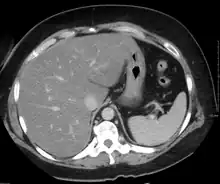

On X-ray computed tomography (CT), the increased fat component will decrease the density of the liver tissue, making the image less bright. Typically the density of the spleen and liver are roughly equivalent. In steatosis, there is a difference between the density and brightness of the two organs, with the liver appearing darker.[11] On ultrasound, fat is more echogenic (capable of reflecting sound waves). The combination of liver steatosis being dark on CT and bright on ultrasound is sometimes known as the flip flop sign.